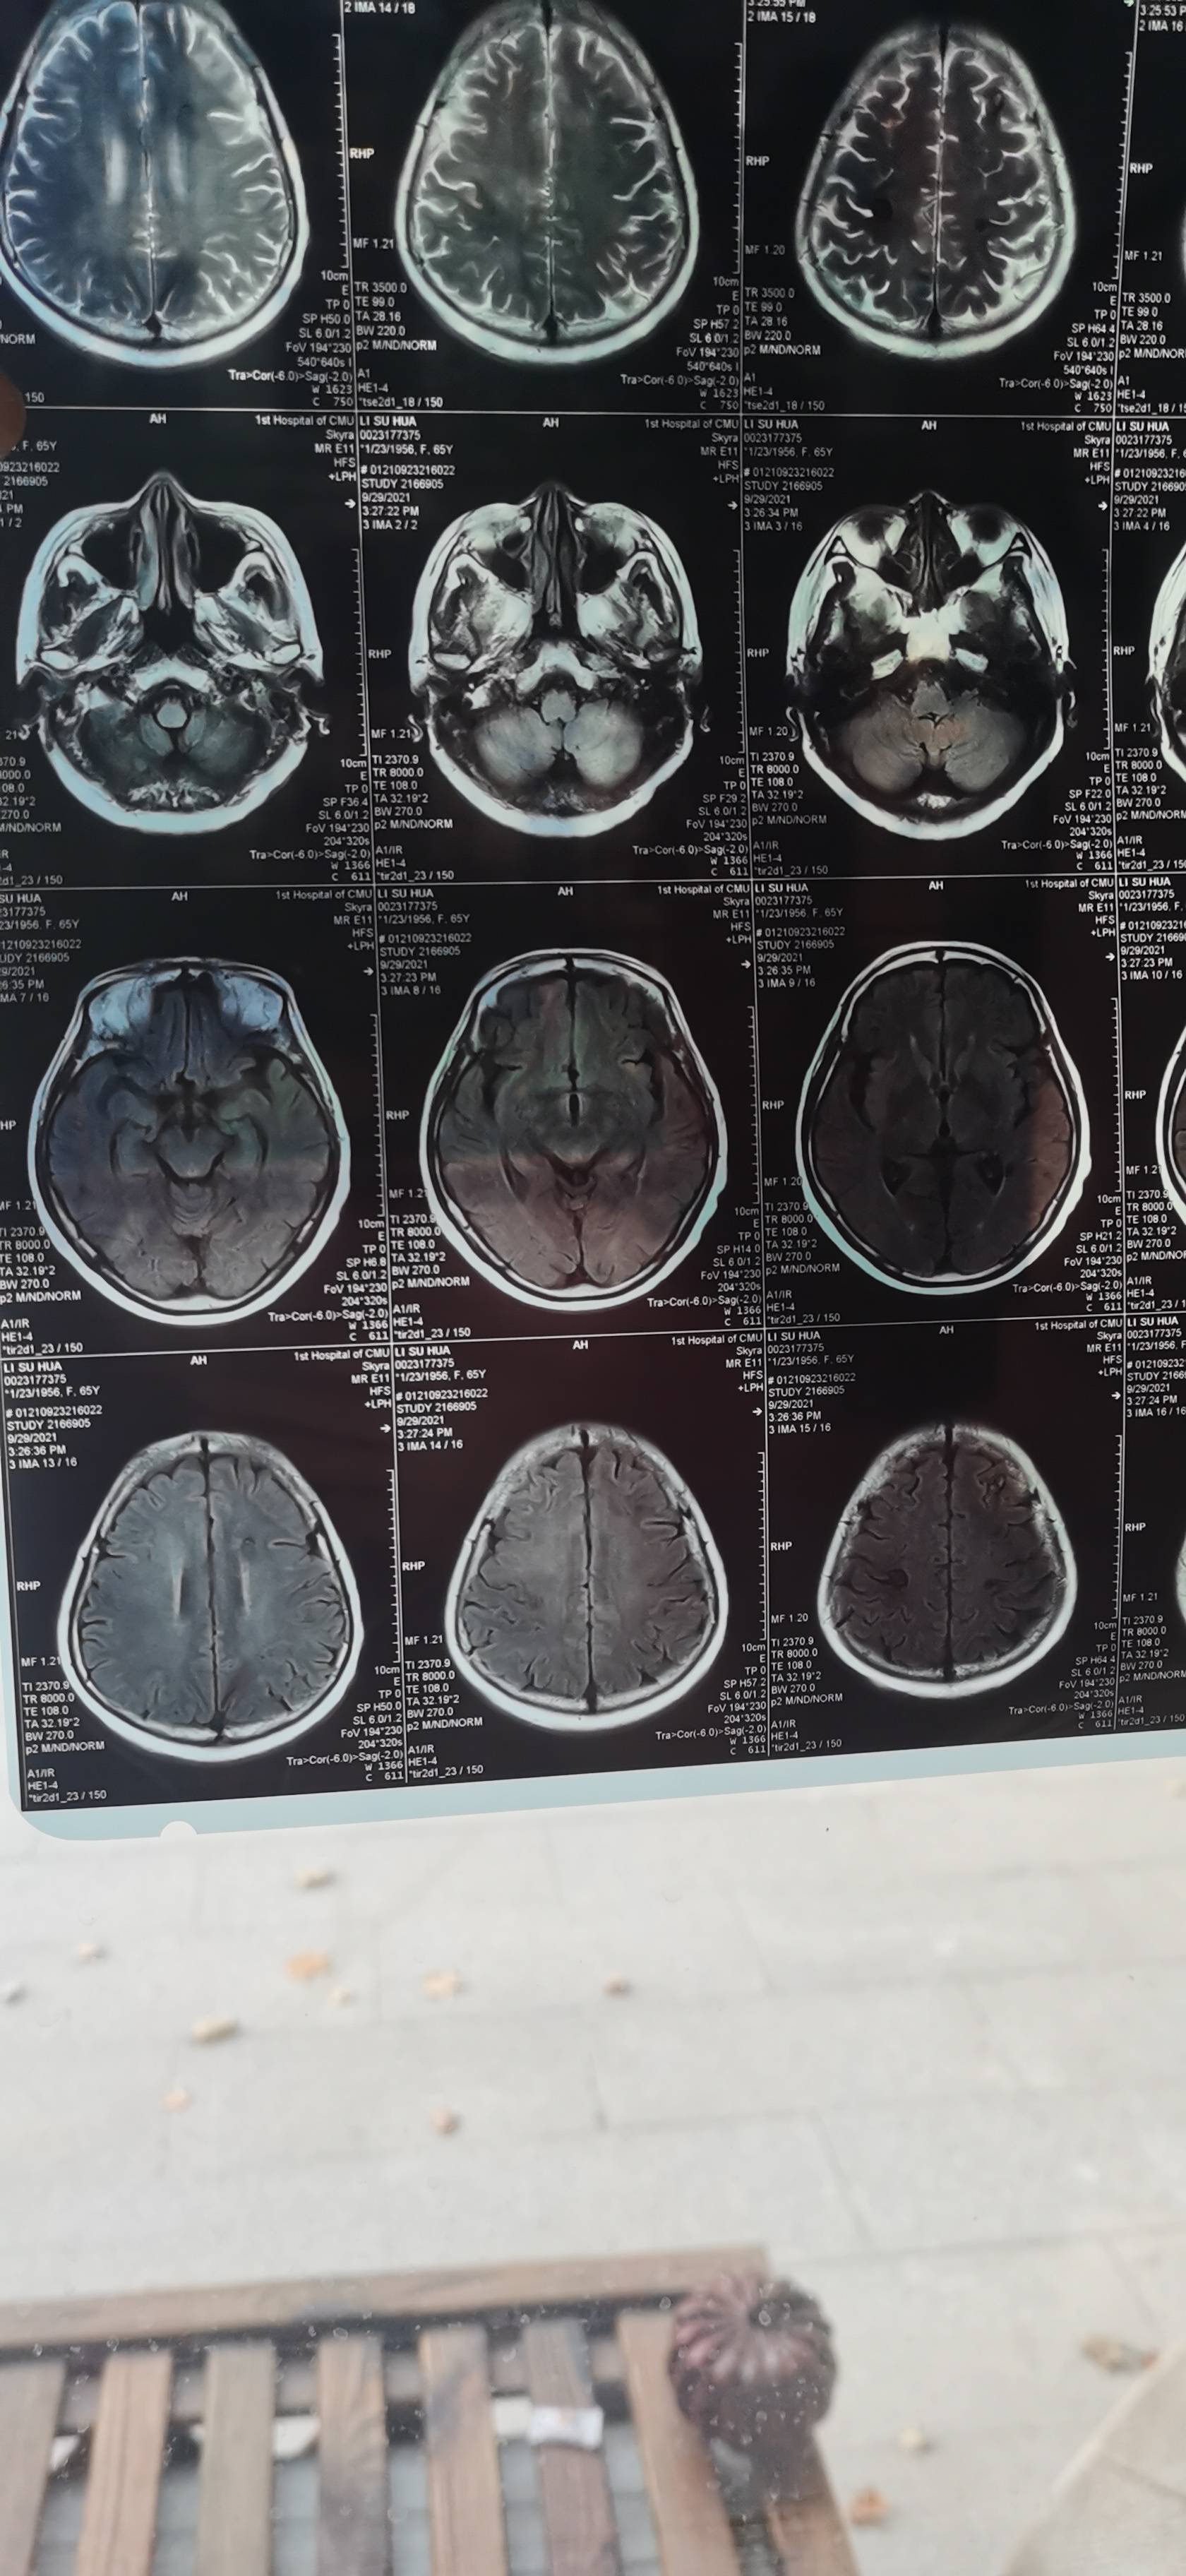

谢谢大家的建议,找到专家看片子了,专家的意见,不是脑膜转移,因为有一个肿瘤离脑干近,做射波刀的时候肯定多少有影响,而且症状也很像脑干受损,让我们观察,目前没有进展,这几天说话比之前利落了,走路不稳也有改善。

没有头疼没有呕吐,步伐依旧不稳,影像依旧无进展,目前达克替尼加奥西替尼联药5天